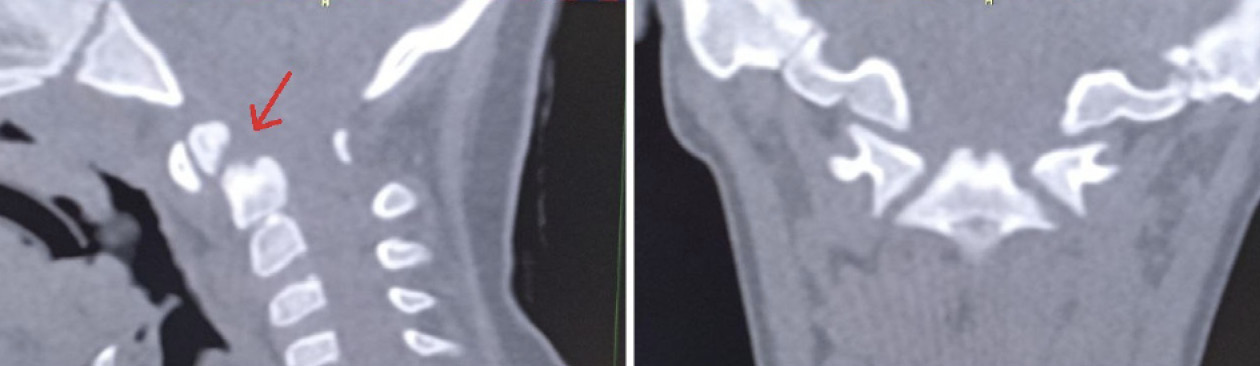

Пациентка Е. 9 лет обратилась на прием с жалобами на ограничение поворотов головой. Со слов матери, в мае 2018 г. ребенку проводилось оперативное лечение по поводу травмы шейного отдела позвоночника. Медицинские заключения не были предоставлены. При осмотре ребенок с синдромом Дауна. Голова по средней линии, пальпация области шейного отдела позвоночника безболезненна, объем пассивных и активных наклонов головы соответствовал нормативным значениям. При этом амплитуда пассивных и активных ротационных движений в шейном отделе позвоночника составила 15° и 20º в каждую сторону соответственно. При последующем ортопедическом осмотре было выявлено нарушение осанки по типу «сутулая спина» по Штаффелю. По данным анализа представленного диска с результатами ранее проведенной мультиспиральной компьютерной томографии шейного отдела позвоночника (дата исследования – май 2018 г.) был выявлен перелом зубовидного отростка С2 позвонка типа 1 по классификации L. D. Anderson и R.T. D'Alonzo, со смещением верхушки зубовидного отростка кпереди [9]. Плоскость перелома зубовидного отростка аксиса косая, края отломков неровные, нечеткие, диастаз между отломками неравномерный (рис. 5).

Рис. 5. Компьютерная томография шейного отдела позвоночника, сагиттальный срез (А), фронтальный срез на уровне зубовидного отростка С2 позвонка (Б). Стрелкой обозначено место перелома зубовидного отростка С2 позвонка

Для оценки ситуации в динамике была проведена КЛКТ, на которой на фоне динамической нерезкости (ребенок был неусидчив) и артефактов от металлоконструкции было отмечено следующее: суставные рентгеновские щели в латеральных атлантоаксиальных суставах: справа – не прослеживается, слева – неравномерно сужена до 0,4 мм в наиболее узком месте (рис. 6). Рентгеновская щель срединного атлантоаксиального сустава в сагиттальной плоскости не прослеживается (рис. 7А), в парасагиттальной плоскости – прослеживается, неравномерная (рис. 7Б). Зубовидный отросток С2 позвонка визуализируется в виде 2 фрагментов, дистальный из которых вместе с передней дужкой С1 позвонка представлен в виде не полностью слитного костного образования. Проксимальный фрагмент, лоцирующийся в проекции верхушки зубовидного отростка С2 позвонка, представлен в виде свободно лежащего отломка с неравномерно склерозированным контуром в проекции диастаза (см. рис. 7). Данная рентгенологическая картина соответствует состоянию после оперативного лечения по поводу травмы шейного отдела позвоночника со стабилизацией металлоостеосинтезом С1–С2 позвонков. Неправильно сросшийся перелом зубовидного отростка С2 позвонка. Частичный анкилоз срединного атлантоаксиального сустава и полный анкилоз правого латерального атлантоаксиального сустава.

Рис. 6. Конусно-лучевая компьютерная томография краниовертебральной области, фронтальный срез на уровне зубовидного отростка С2 позвонка

Рис. 7. Конусно-лучевая компьютерная томография краниовертебральной области, сагиттальный срез (А), парасагиттальный срез (Б). Стрелкой отмечено место анкилоза срединного атлантоаксиального сустава. Двойной стрелкой обозначен свободно лежащий апикальный костный фрагмент зубовидного отростка аксиса